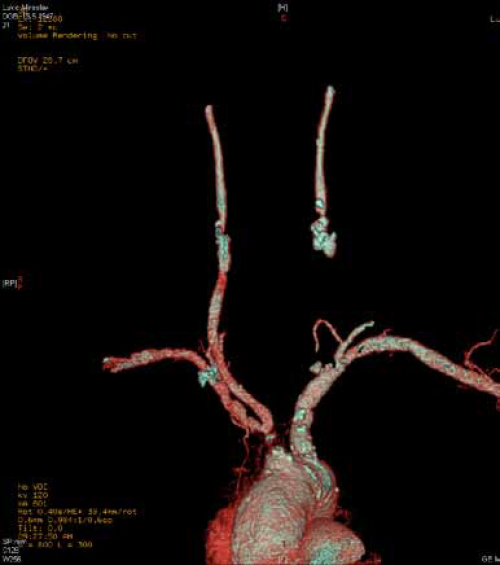

Multislice Computed Tomography Angiography (MSCT) ili Multidetector Computed Tomography (MDCT) karotidnih arterija značajno skraćuje vreme trajanja pregleda, količinu zračenja i kontrastnog sredstva, daje manje artefakata i pruža mogućnost kvalitetne 3D rekonstrukcije. Danas, posle više generacija MSCT aparata možemo reći ovi nalazi imaju brojne prednosti u poredjenju sa konvencionalnom angiografijom.

MSCT angiografija pokazuje stepen stenoze i prirodu plakova, ali i morfologiju karotidnih arterija i odnos sa ostalim strukturama vrata, kao i Willisov poligon. Neophodno je planiranje rekonstruktivnih zahvata trastorakalnim putem. MSCT 3D tehnikom se prikazuju morfološke promene karotidnih arterija u vidu angulacija, elongacija, kinkinga i coilinga. Prisustvo prizidne tromboze se može naslutiti arteriografski, a videti Duplex-sonografski i MSCT-om.

MSCT angiografija, princip rada

MSCT – precizna analizua morfologije lezija supraaortalnih arterija

Skoro potpuna okluzija brahiocefaličkog trunkusa sa dugačkom totalnom trombozom zajedničke karotidne arterije levo